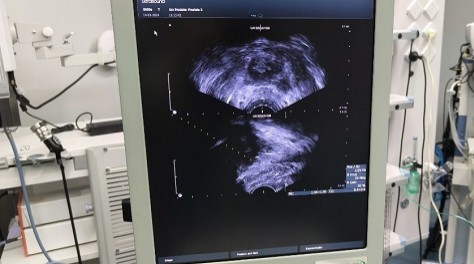

近期,我院泌尿外科通过开展新技术,针对经筛查的10余例高度可疑前列腺癌患者进行“超声引导下前列腺穿刺活检术”;活检结果明确为前列腺癌,为患者提供准确的治疗方向。该技术是前列腺癌诊断的“金标准”。

超声引导下前列腺穿刺活检术的成功开展,是我院泌尿外科肿瘤防治方面的新突破,填补了我县此项技术的空白,标志着我院泌尿外科治疗水平再上一个新台阶,为实现我县前列腺疾病患者的早期诊治奠定了良好基础,也为县域内患者带来福音。